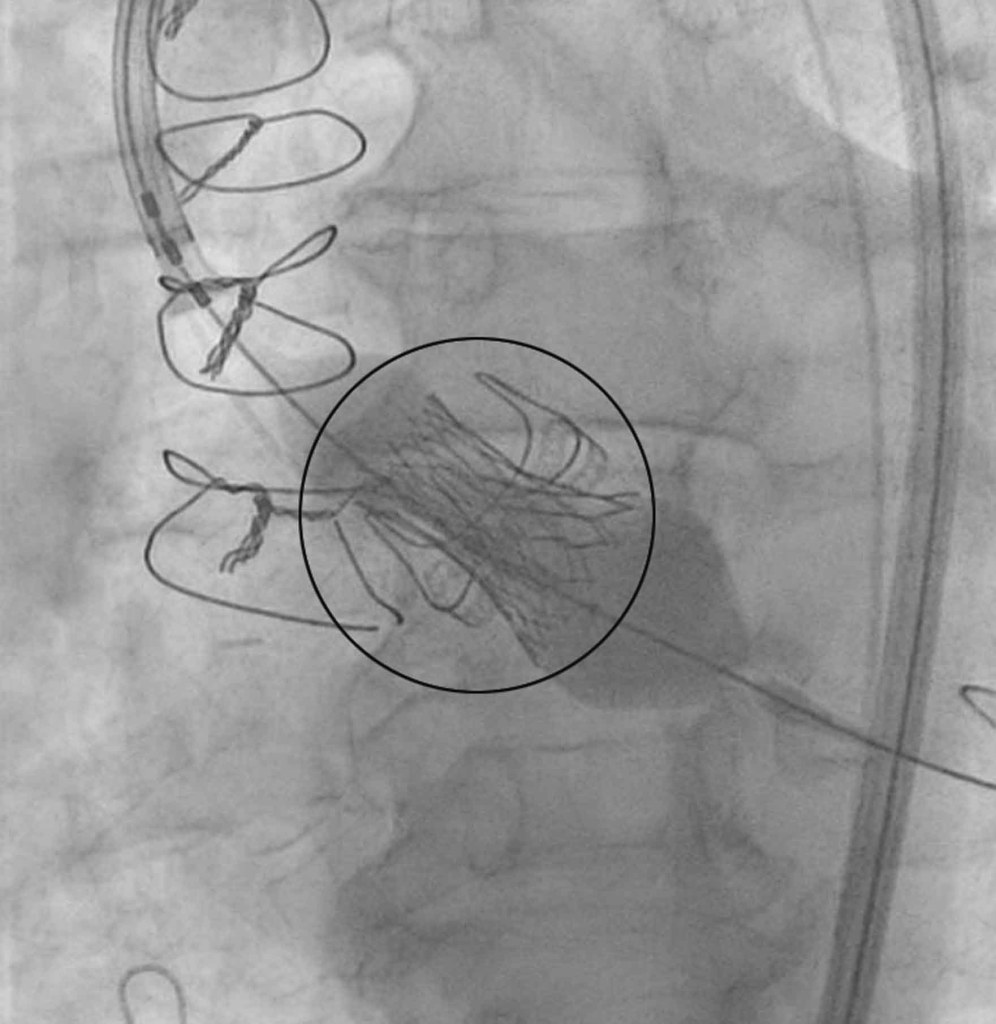

Although the decision was to implant another tissue valve, it was done through TAVI, in one of the Cardiac Centre’s three catheter labs.

“It’s fascinating. You have three TV screens in front of you and you’re watching it live. I wasn’t sedated or anything,” he said.

“There was a sharp scratch and a little bit of general discomfort as they moved the catheter around inside me. It was all thoroughly explained, what was going to happen and what I would feel at the various points.

“Because I already have a surgically-implanted valve, the new valve was going in through that so they knew exactly where to locate it.

“It was literally 30 seconds where they were saying, okay, they were happy with it. A little bit of electrical stimulus on the heart to make it flutter but not pumping blood at that point. And – bang. This new valve was in place and the various wires were redacted.

“The doctors were looking at the screen and saying it fitted perfectly; there was no seepage through the valve. It’s pumping perfectly. One said, you may even be going home today – it was that satisfactory a result.”